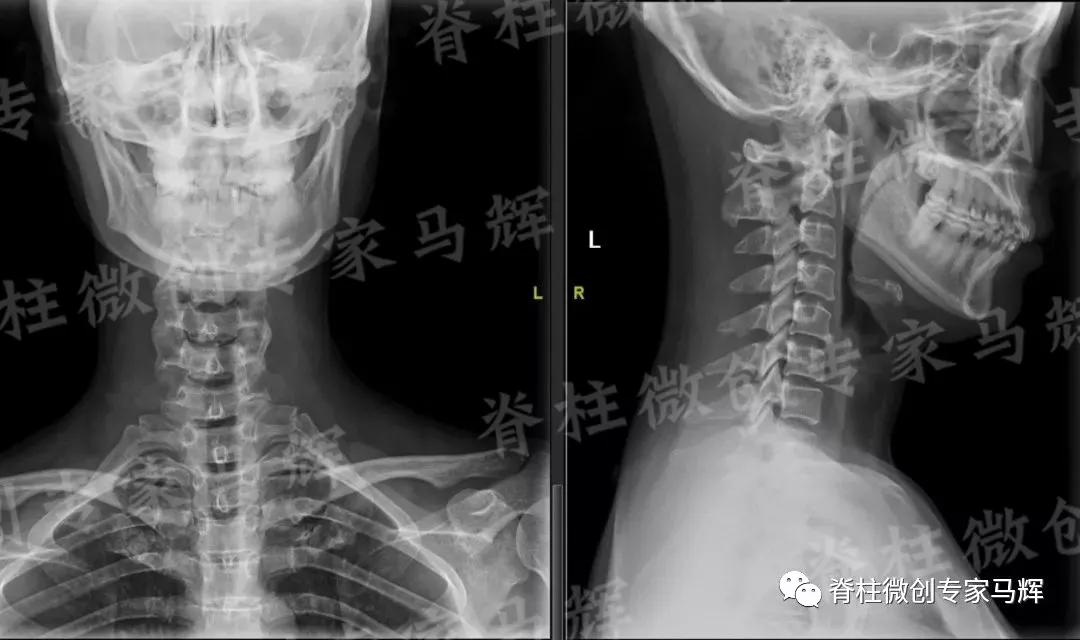

马主任仔细给患者做了检查,发现疼痛范围累及颈背部,及右上臂、前臂至手掌桡侧三指,无胸背部束带感,无行走不稳。根据影像学结果,诊断缪女士患6/7椎间盘突出症,属于神经根型颈椎病。

(术前)